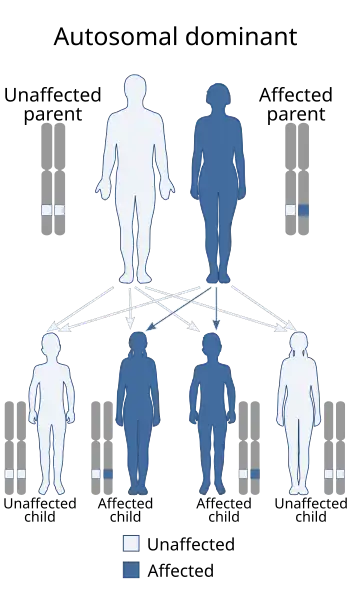

| Miller–Dieker syndrome is inherited in an autosomal dominant manner | |

It may be a random event during the formation of reproductive cells or in early fetal development or due to familial chromosomal rearrangement called chromosomal translocation. In less than 20%, inheritance is through an autosomal dominant pattern. The parent is usually unaffected, but carries a particular chromosomal rearrangement called a balanced translocation, in which no genetic material is gained or lost. Increased rate of unexplained fetal loss may be observed in MDS carriers with balanced translocations although they may be otherwise asymptomatic.[5] However, they can become also unbalanced as they are passed to the next generation. Miller–Dieker syndrome is usually not inherited. The deletion event occurs randomly during gametogenesis (formation of eggs or sperm) or in early foetal development. Therefore, no history of the disorder is usually seen in their families.